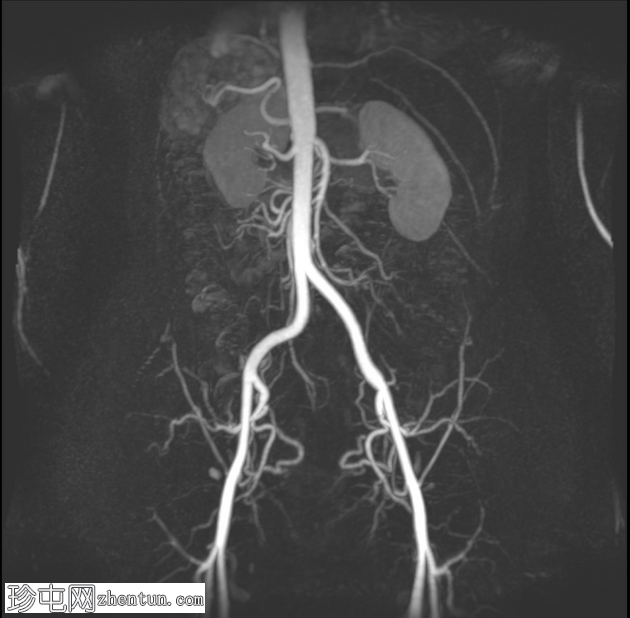

冠状位

血管扭转MIP序列

8.png